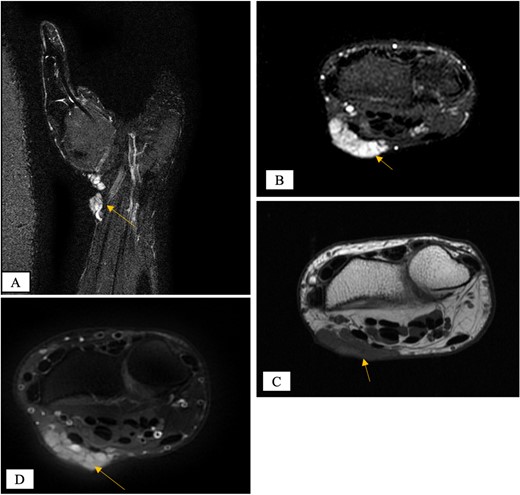

X-ray showed a well-defined non-aggressive lytic bony lesion of the first metacarpal bone (Fig. 1). Magnetic resonance imaging (MRI) showed a grossly stable skin and subcutaneous multilobulated soft tissue mass located at the palmar aspect of the wrist joint measuring 6 × 2 × 3.3 cm3 in its maximum anteroposterior, transverse and craniocaudal dimensions, respectively (Figs 2 and 3). The lesion showed low and high signals in T1 - and T2-weighted images with homogenous contrast enhancement. The lesion was inseparable from the flexor carpi radialis and palmaris longus tendons without definite invasion or encasement. The lesion was not in continuity, however, with the serpiginous lytic bony lesion noted at the first metacarpal bone exhibiting low T1 and high T2 signals with peripheral enhancement and no cortical destruction or associated soft tissue component (Fig. 4).

MRI of the left distal forearm showing cutaneous and subcutaneous lobulated mass at the volar aspect of high T2 and low T1 signals with diffuse enhancement. (A) Sagittal T2-weighted fat saturated image. (B) Sagittal T1-weighted image.